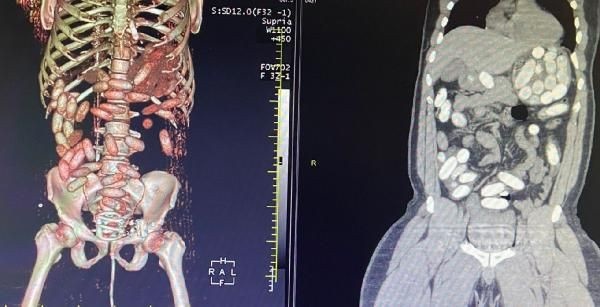

Gümrük Muhafaza ekiplerince savcılık talimatı doğrultusunda detaylı bilgisayar tomografi çekilmesi için sağlık kuruluşuna götürülen 6 yolcunun yapılan tarama ve muayenelerinde 761 adet ve toplam ağırlığı 10 kilo 420 gram kokain tespit edildi.

Yolcuda, 'yutucu' tespit cihazı ve ardından sağlık kuruluşunda yapılan muayene sonucu 48 adet kapsül ve toplam ağırlığı 760 gram kokain ele geçirildi.